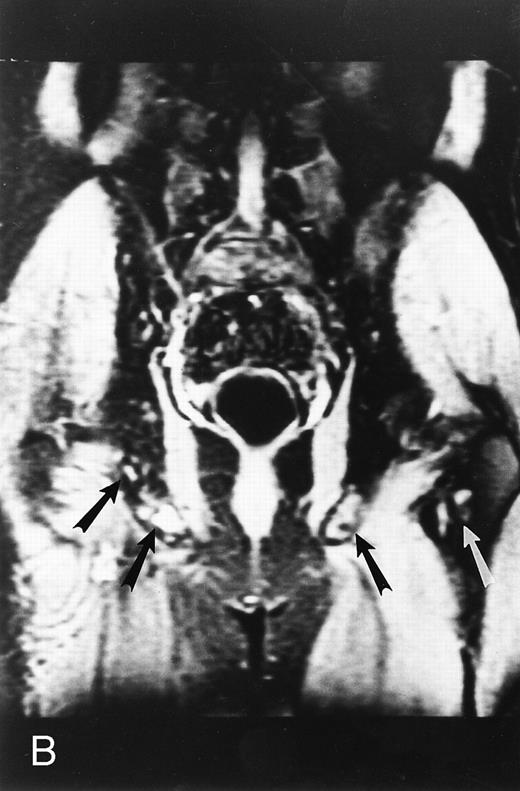

A 75-year-old woman with Waldenstrom macroglobulinemia: T1-weighted (600/20, TR/TE) axial (A) and sagittal T1-weighted (600/20, TR/TE) precontrast (B) and postcontrast (C) MR images of the lumbosacral spine. Note diffuse pattern of marrow infiltration and enlarged retroperitoneal lymph nodes (arrows). The abnormal marrow is isointense to the intervertebral discs on the precontrast image and enhances markedly becoming hyperintense to the discs on the postcontrast image.